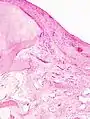

Diagnosis is made with reasonable certainty based on history and clinical examination.[51][52] X-rays may confirm the diagnosis. The typical changes seen on X-ray include: joint space narrowing, subchondral sclerosis (increased bone formation around the joint), subchondral cyst formation, and osteophytes.[53] Plain films may not correlate with the findings on physical examination or with the degree of pain.[54]